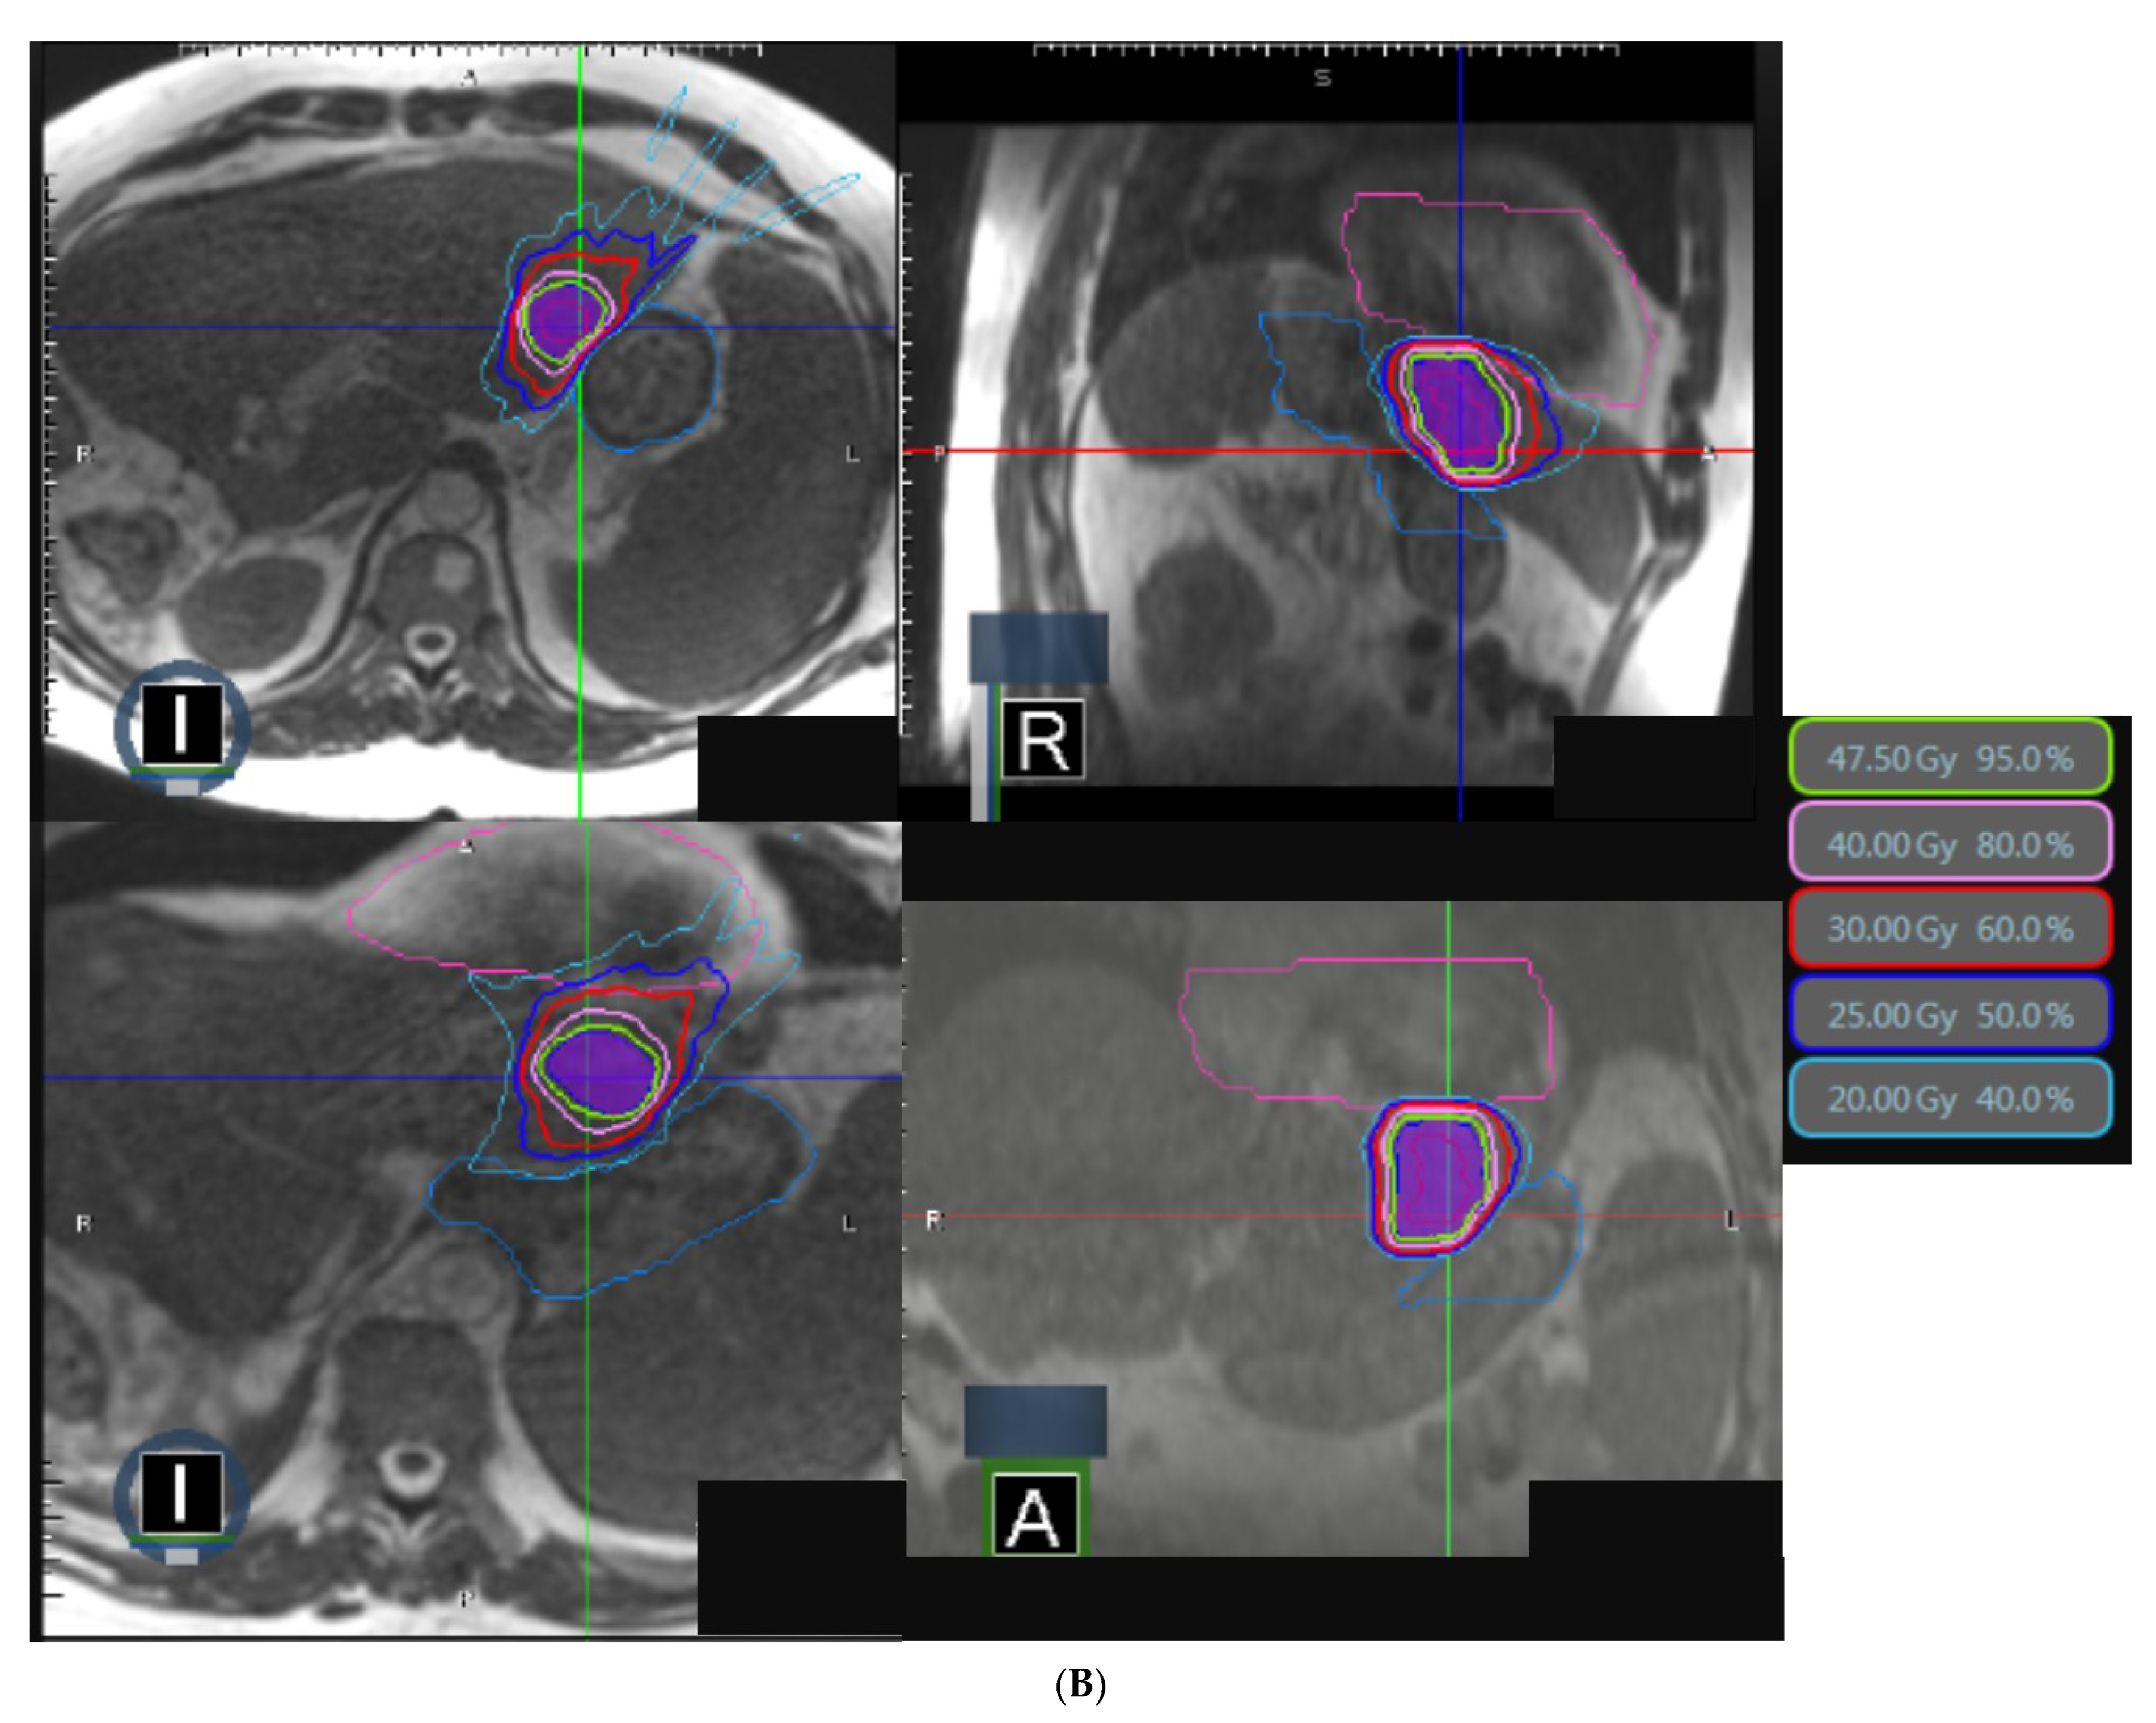

| PTV | |

| V95% (%) V100% (%) D95% (Gy) D1cc (Gy) | 95.9 (71.6–98.9) 50.0 (49.2–90.8) 47.5 (26.9–58.0) 52.0 (41.2–63.1)) |